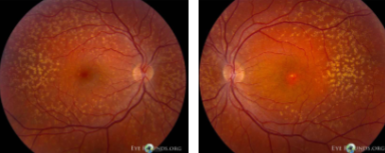

drusen

multilpe, discrete, round, slightly elevated, variable sized, yellow/white sub-RPE deposits in the macula & posterior pole b/t the RPE & Bruch’s membrane

bilateral

clustered in macular or paramacular area

tend to increase in # & size but can fade from view & decrease in number

change in size/shape/distribution/color/consistency w/ time

hard drusen

yellow, punctate, calcific

can become crystalline in appearance or occasionally polychromatic or golden sparkling indicative of cholesterol deposits

low risk of MNV

FA shows early, well defined focal hyperfluorescence w/o leakage

often clustered & can extend out of the vascular arcades & into the equatorial retina

soft drusen

larger, pale yellow or gray-white, placoid or dome-shaped, less well-defined

may coalesce to appear similar to a serous detachment of the RPE

FA demonstrates early hyperfluorescence that does not leak & fades midway through

increased risk of MNV

drusen

drusen

hard drusen

soft drusen

soft drusen

soft drusen

soft drusen